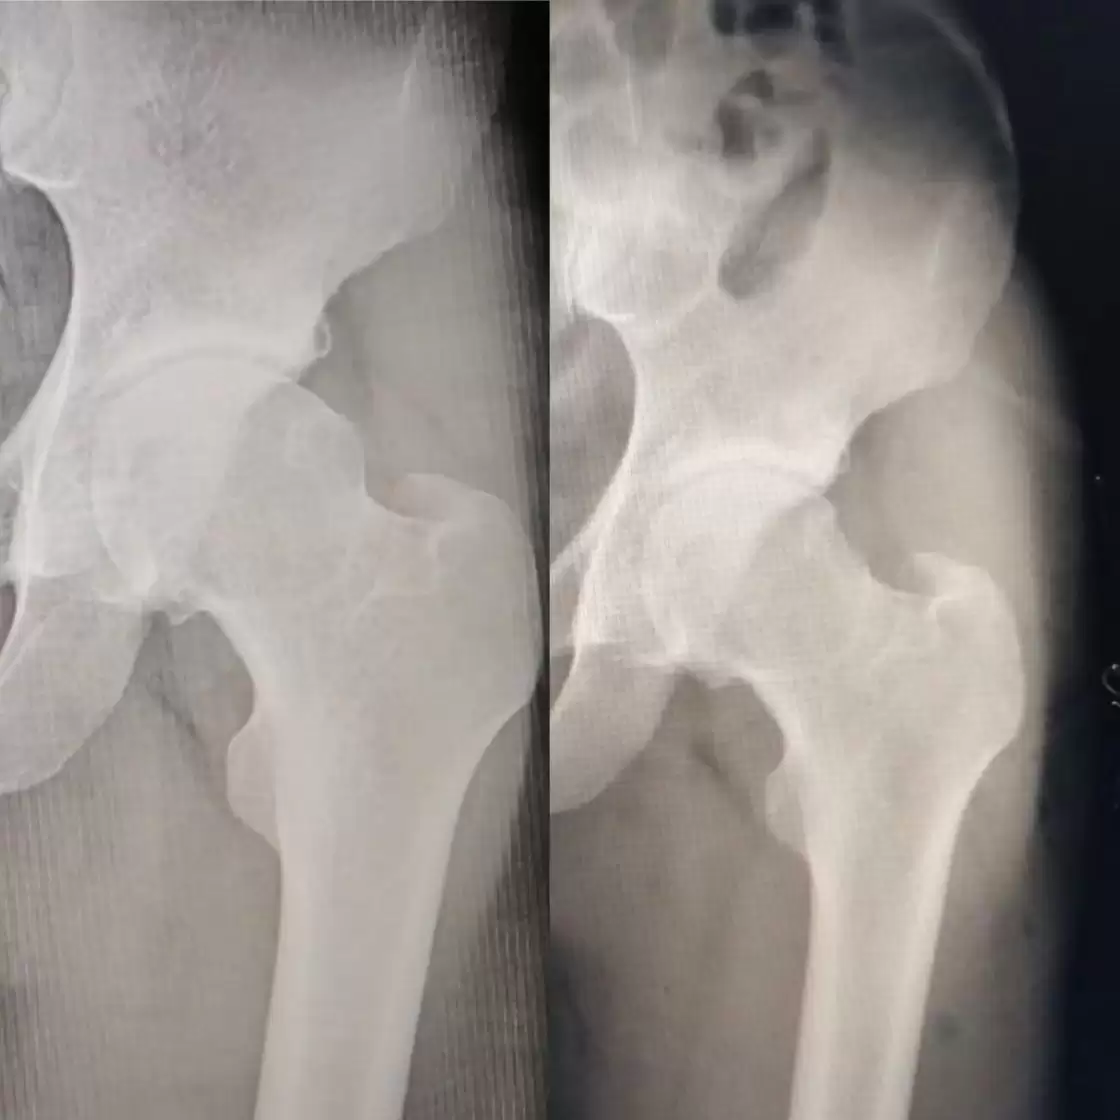

Kalça

Fotoğraflar